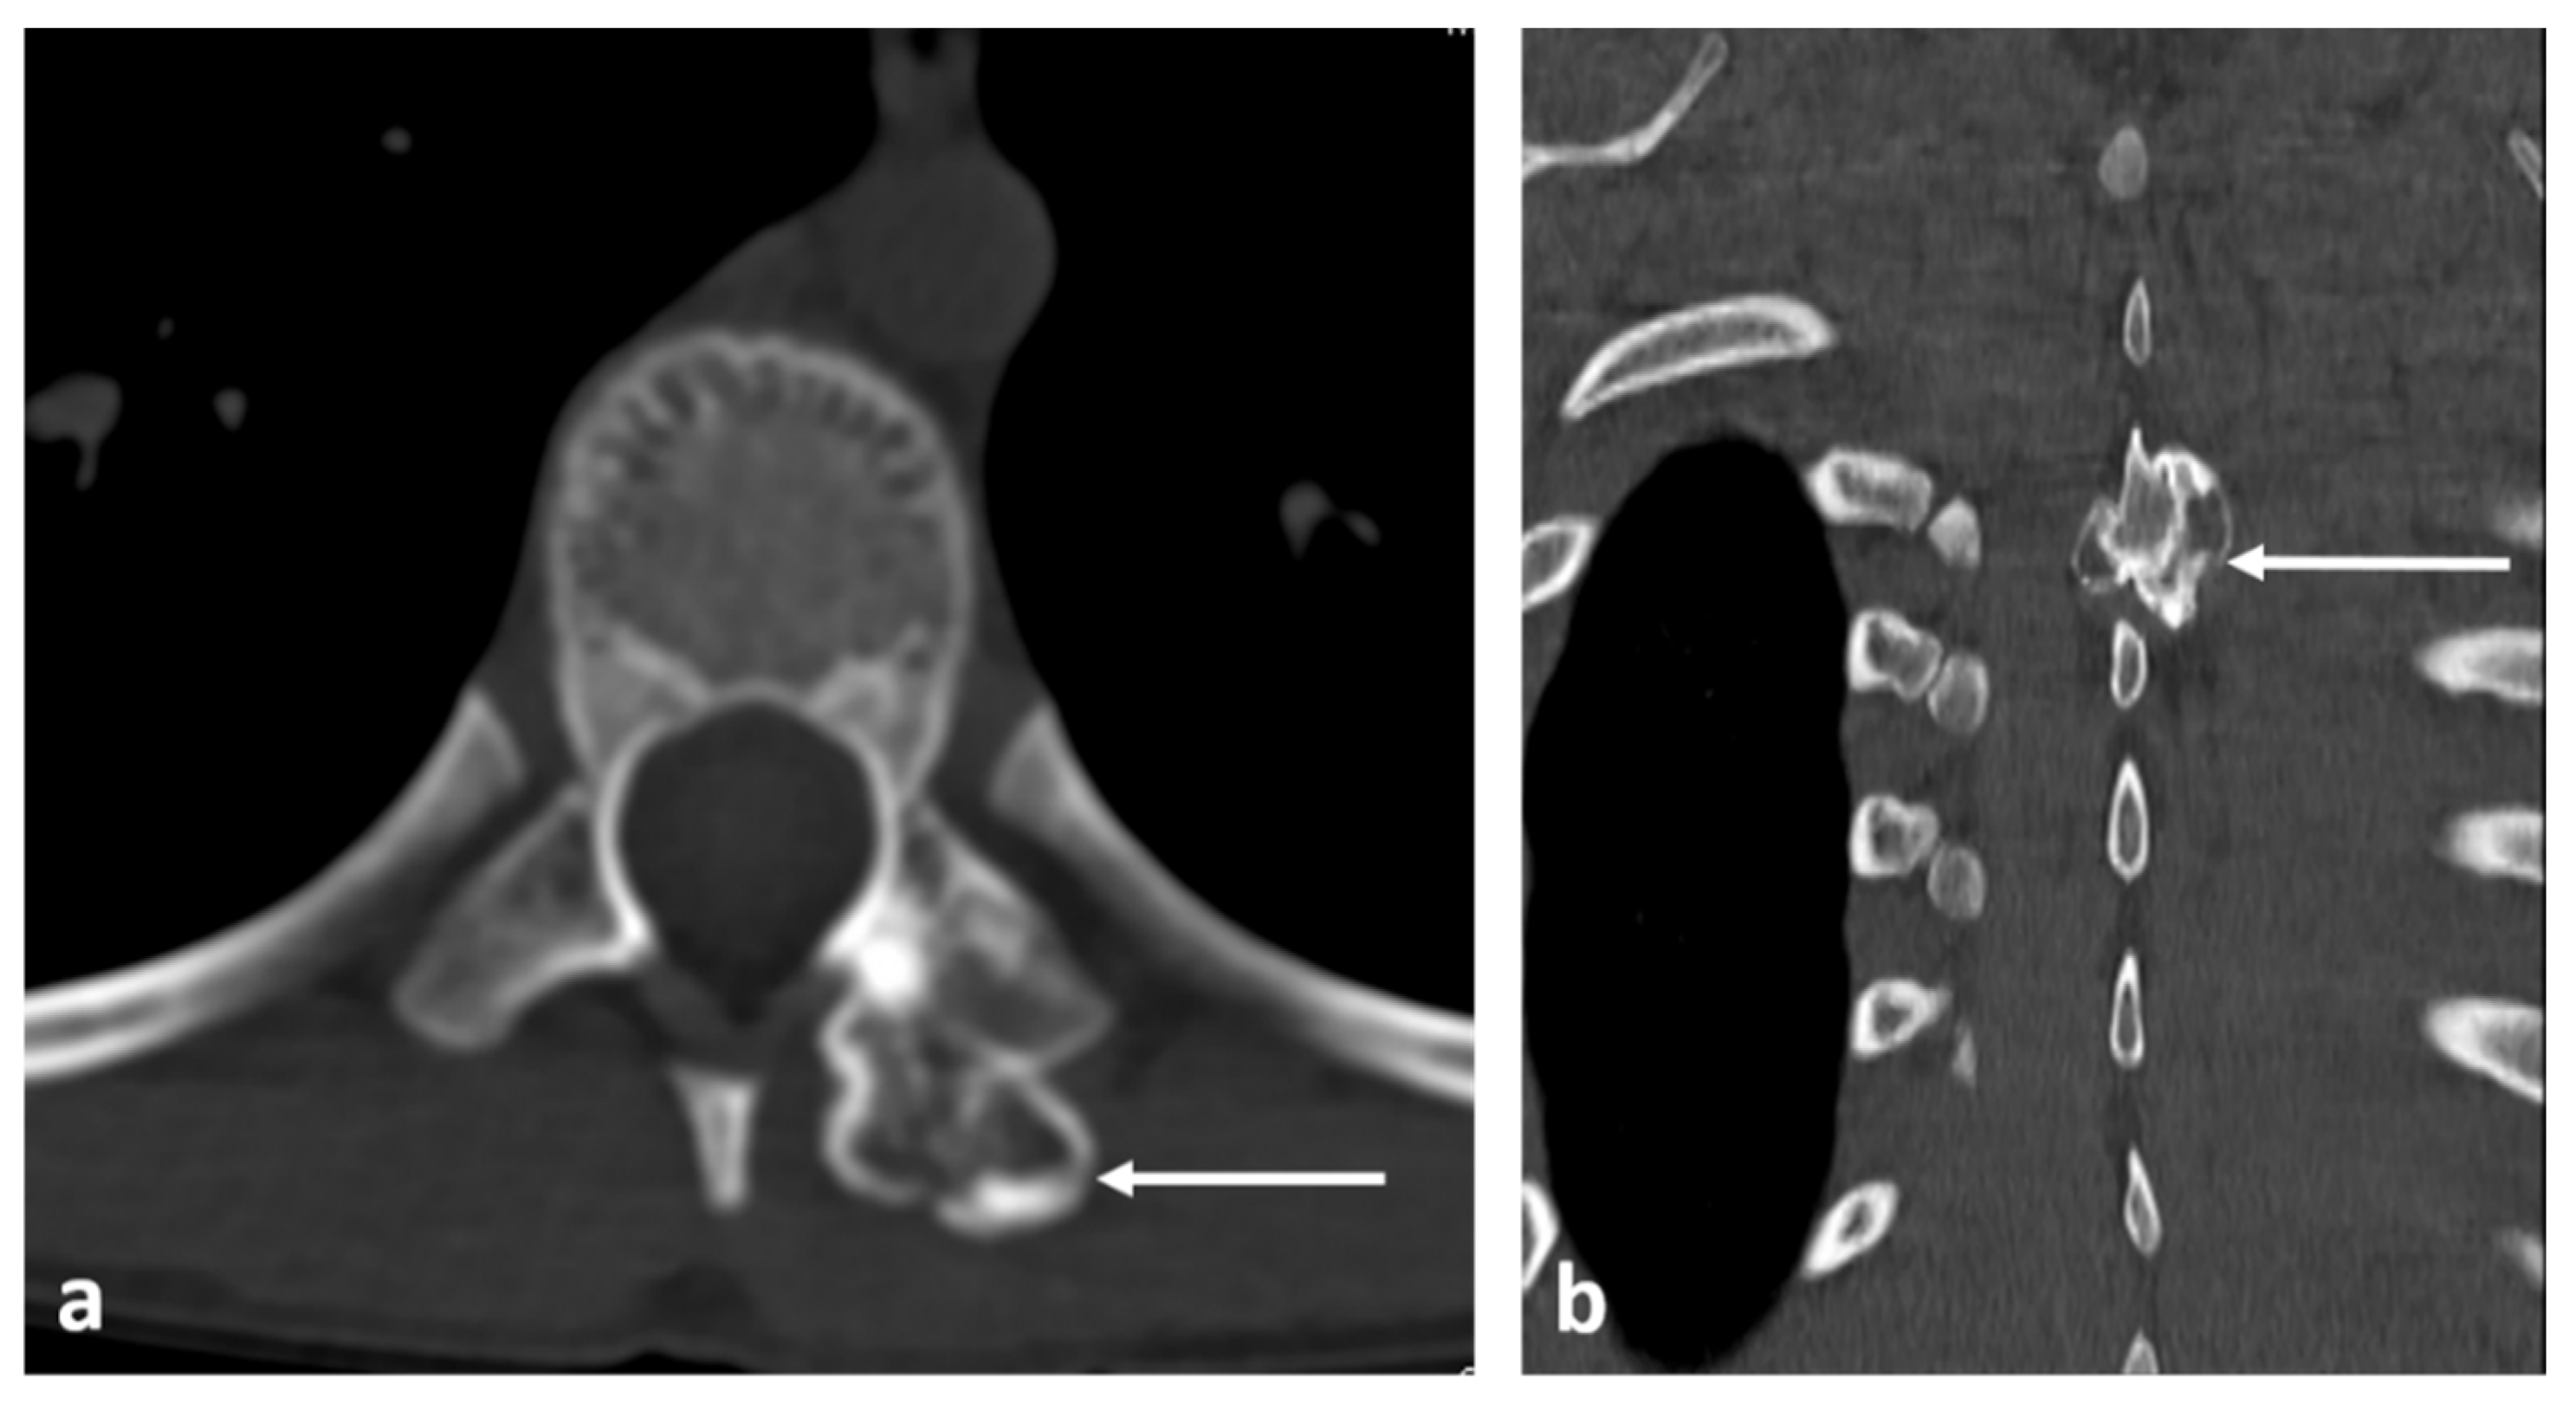

3.2. Osteoid Osteoma

| Osteoid osteoma | Lucent nidus, usually 2–10 mm. May be surrounded by sclerotic rim. | Surrounding marrow oedema on fluid sensitive sequences (best seen on STIR). Nidus can be occult on MRI. |